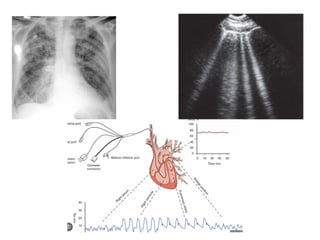

Definition of Heart Failure

Clinical syndrome with symptoms and/or signs

caused by a structural and/or functional cardiac

abnormality and corroborated by elevated natriuretic

peptide levels and/or objective evidence of pulmonary

or systemic congestion..

Imaging (e.g.,

echocardiogram,MRI)

Corroborating Evidence

Elevated Natriuretic Peptides (BNP or NT-proBNP)

and/or

Objective Evidence of Congestion (fluid backup)

from imaging (X-ray, ultrasound, or invasive

hemodynamic measurement).